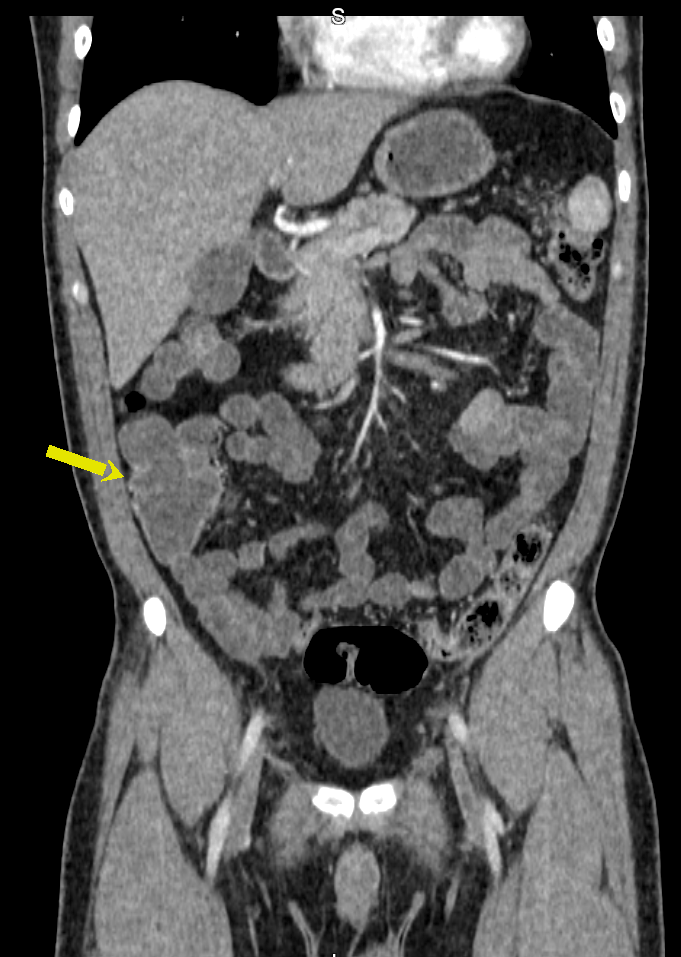

A Enterografia por Tomografia Computadorizada é um exame que estuda o intestino delgado, permitindo diagnóstico de diversas doenças que afetam este órgão, como a Doença de Crohn. O exame também é conhecido como enterotomografia. Assemelha-se à tomografia computadorizada tradicional com contraste.

A Enterotomografia difere da TC convencional de abdômen pela utilização de grandes volumes de contraste oral e cortes finos, com reconstruções multiplanares. As principais indicações são para as seguintes situações: avaliação de sangramento gastrointestinal obscuro, diagnóstico e acompanhamento de doença inflamatória intestinal, especialmente a doença de Crohn, e pesquisa de neoplasias intestinais.

Contrastes orais neutros permitem a melhor distinção de segmentos com realce mural aumentado, de massas hipervasculares e de outros processos inflamatórios e vasculares.